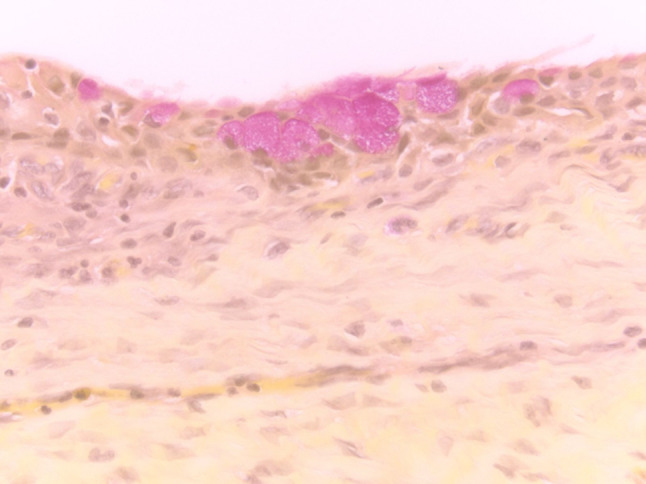

Fig. 13.

(Left) Inflammatory cyst lined by squamous metaplasia (H&E stain, magnification × 40). (Right) FNA of cyst contents from an inflammatory cyst containing scattered atypical metaplastic squamous cells, scant inflammatory cells and numerous orangeophilic crystalloids (Papanicolaou stain, magnification × 60)